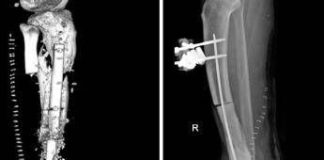

Batterio gli ‘mangia’ la carne, operazione al Gemelli gli salva gamba...

(Adnkronos) - Un mix di batteri 'mangia-carne' lo aveva infettato dopo una banale ferita cutanea, consumandogli buona parte di una gamba fino alla caviglia....